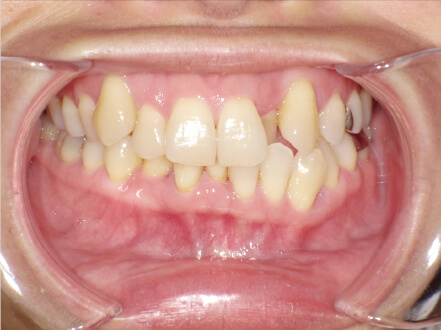

叢生の症例

41歳

女性

相談内容

横から見た時のガタガタが気になる

カウンセリング・診断結果

インビザライン、正中は上11に合わせていく、抜歯・拡大装置・IPR・アタッチメントOK

治療内容・方法

アライナー矯正

術後の経過・現在の様子

クリアライナー使用

治療のリスク

痛み・歯根吸収・歯肉退縮・虫歯・後戻り

費用・治療期間

880,000円、7ヶ月